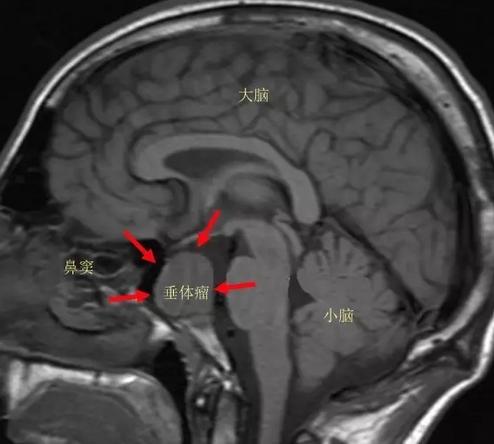

随后,为赵先生安排了脑部核磁共振检查,检查结果显示他的脑垂体上长了个鹌鹑蛋大小的垂体腺瘤,该垂体瘤造成肢端肥大症,导致生长激素过度分泌,使身体出现一系列的变化,最明显的就是外貌的改变。若垂体腺瘤继续长大,轻则导致视力下降、眼睛失明,重则引起头痛、呕吐、昏迷乃至死亡。

垂体是一个位于头颅内的内分泌器官,是机体神经-内分泌系统所有腺体中最重要和最复杂的器官,是机体内分泌系统的“指挥中枢”(master gland)。大脑底部有一块骨头叫蝶骨,蝶骨上有一个像马鞍形状的小窝,称蝶鞍,脑垂体就舒舒服服地躺在里面。